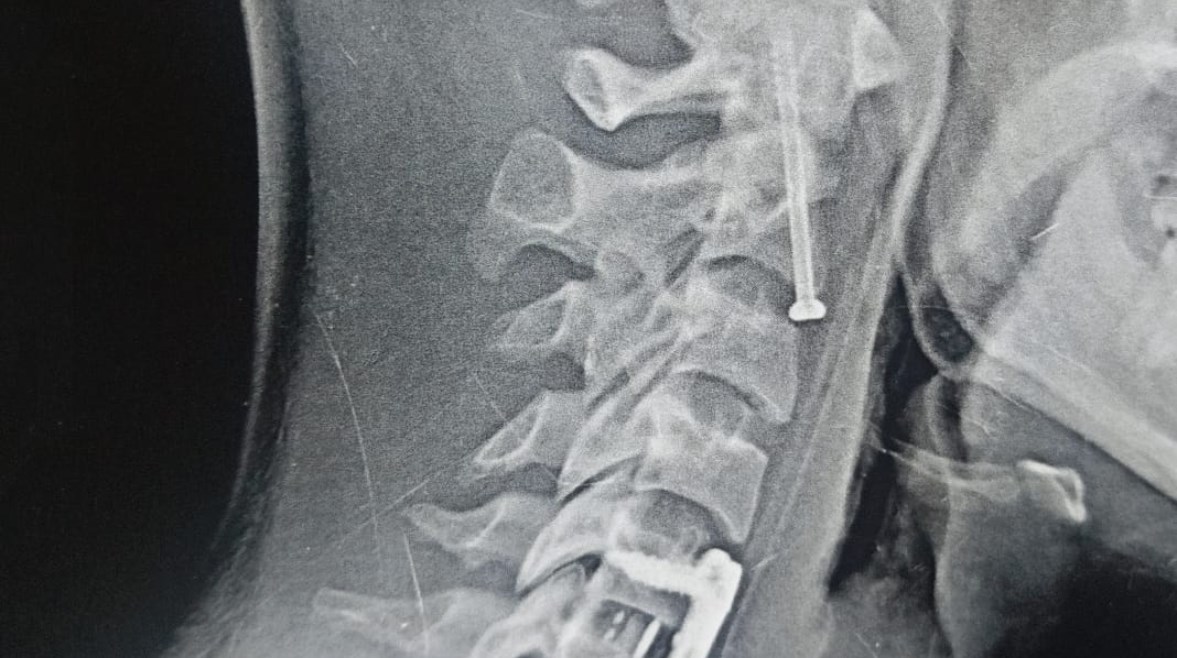

أشعة أجريب للمريض

وكان قسم الاستقبال والطوارئ بمستشفيات جامعة بنها قد استقبل المريض عقب سقوطه من علو، وبالفحص والأشعة تبين إصابته بكسر في الفقرة العنقية الثانية، وهي من أكثر المناطق خطورة لقربها من جذع المخ المسؤول عن الوظائف الحيوية، إضافة إلى وجود تزحزح فقاري بين الفقرتين الخامسة والسادسة.

وأُجريت الجراحة تحت إشراف وتوجيه الدكتور إسلام أبو الفتوح رئيس قسم جراحة المخ والأعصاب، والدكتور إيهاب سعيد رئيس قسم التخدير، حيث تمكن الفريق الطبي من تثبيت كسر الفقرة العنقية الثانية بدقة عالية، إلى جانب تثبيت التزحزح الفقاري بين الفقرتين الخامسة والسادسة باستخدام شريحة ومسامير وقفص عنقي.